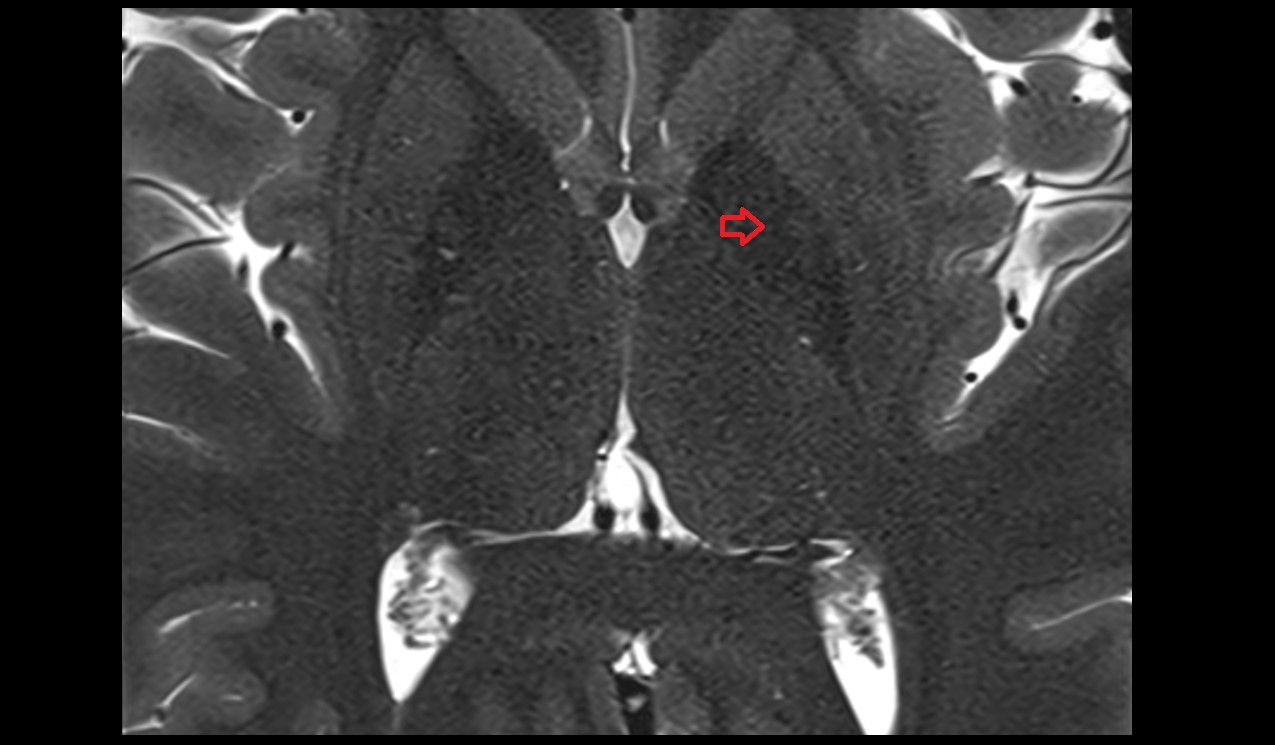

- Hippocampus